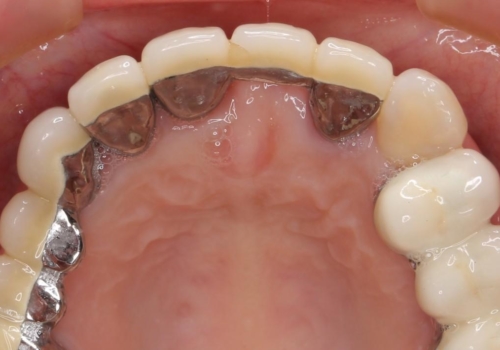

前歯ブリッジのやりかえ

- 前歯の審美障害、見た目の改善を希望され来院されました。

歯肉縁下カリエスも認められるため、挺出を行いセラミックブリッジを審美的に新製します。

- 47万円(仮歯×3・ファイバーコア×2・ジルコニアクラウン×3 歯の挺出)費用は治療当時の料金となります